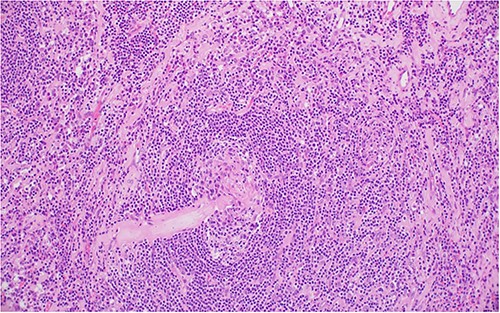

The patient underwent right laparoscopic adrenalectomy with a transperitoneal approach. A dark yellow tumor measuring 11 × 7 × 3.5 cm was removed en bloc (Fig. 2). Postoperative convalescence was uneventful and the patient was discharged home after 2 days, with discontinuation of antihypertensive medications. Microscopic examination revealed a mixed hyaline vascular and plasma cell variant type of Castleman lymphadenopathy (Figs 3 and 4). Immunohistochemistry showed a mixed pattern of CD20 and CD3, IgD that highlighted the expanded mantle zones and CD138-positive plasma cells that showed polytypic expression of Kappa and lambda immunoglobulin light chains. Immunostaining for Human herpesvirus 8 (HHV-8) was positive. A diagnosis of a unicentric mixed variant of Castleman lymphadenopathy was made.

(A), Regressed germinal center shows hyalinized blood vessels, dendritic cells and mantle zone forming an ‘onion skin’ arrangement; (B), the hyalinized blood vessels together with the atretic follicles and concentric mantle zone import a ‘lollipop’ appearance.

Two germinal centers fused and surrounded by one mantle zone—‘twinning’.